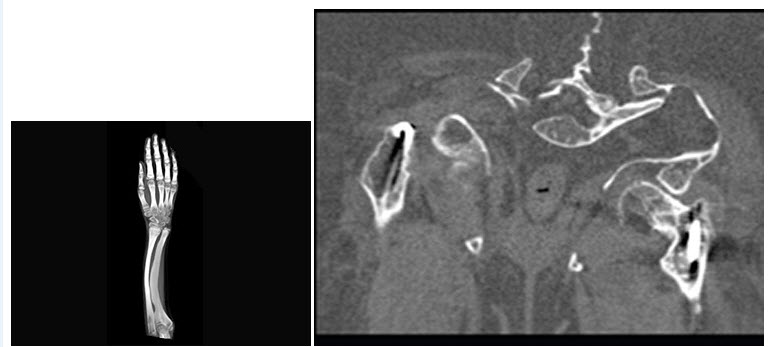

23、单项选择题

男,7岁,外伤后1个月,当时右上臂上部局部肿痛,行夹板固定。根据CT平扫片,最可能的诊断为()

A.骨囊肿

B.骨纤维异常增殖症

C.动脉瘤样骨囊肿

D.干骺端结核

E.骨肉瘤